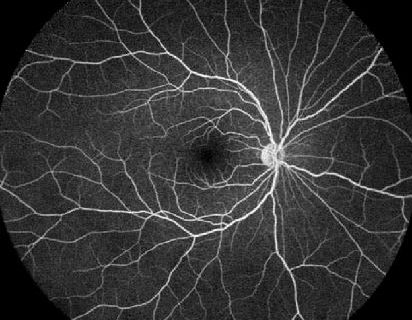

Φλουοροαγγειογραφία

Στο τέταρτο κεφάλαιο της εκπαιδευτικής ενότητας «Διαγνωστικές εξετάσεις – ερμηνεία και αξιολόγηση» παρακολουθούμε το ταξίδι της χρωστικής φλουορεσκεΐνης στα αγγεία του βυθού. Μελετώντας τα ιδιαίτερα χαρακτηριστικά των αγγειακών δομών και των φραγμών τους, συναρτήσει των βιοχημικών ιδιοτήτων του μορίου της φλουορεσκεΐνης και του χρόνου, λαμβάνουμε πληθώρα πληροφοριών που ρίχνουν φως στη διαγνωστική διερεύνηση των παθήσεων…